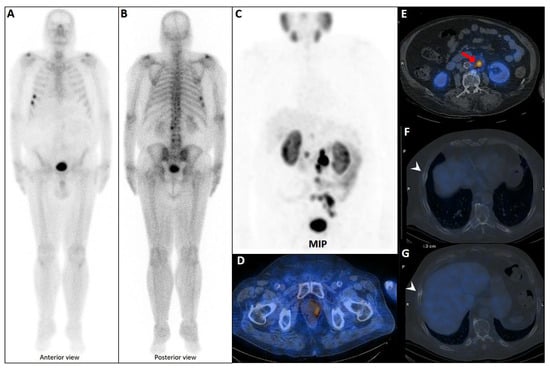

In oligometastatic PCa, defined by a limited disease burden of up to five metastatic sites, the identification of rib lesions is pivotal for volume stratification and therapeutic planning. Only 10–20% of PSMA-avid rib lesions in this setting are truly metastatic [113]. A single metastatic rib lesion may classify the disease as low-volume, making it eligible for MDTs like SBRT to delay systemic treatment and disease progression while preserving quality of life [156]. Conversely, presence of at least three additional axial bone or concurrent visceral metastases may indicate high-volume disease, necessitating aggressive systemic therapies such as ADT, ARPIs, and possibly docetaxel [150,157]. The presence and pattern of rib lesions thus create a clinical dichotomy, underscoring the importance of tailored management guided by advanced imaging, such as PSMA PET/CT, and multidisciplinary decision-making (Figure 6) [158]. Accurate characterization of rib lesions across these settings is essential to balance the risks of overtreatment and undertreatment, ensuring optimal patient outcomes.

Figure 6.

Complete discordant findings between PSMA and bone scan. 61-year-old male referred for staging that transrectal ultrasound-guided prostate biopsy showed GS 4 + 3 (12 of 12 cores involved), perineural invasion (+), and serum PSA level = 17 ng/mL. A whole-body bone scan revealed multiple increased tracer uptake in bilateral rib (A). 99mTc-PSMA SPECT/CT revealed no abnormal tracer uptake (B). Considering discordant findings in the 99mTc-PSMA and bone scan, the referring physician decided to request a 68Ga-PSMA PET/CT. The scan showed (C) multiple foci of increased activity in the left side of the prostate gland (D) as well as two foci of increased activity in bilateral ribs with no density changes on the corresponding CT images (SUVmax up to 3.84) (blue arrowhead, E,F). The rib lesions were finally considered as equivocal. Ultimately, the patient underwent RP and nadir PSA was 0.02 ng/mL.

In contrast, multiple rib lesions present a more complex diagnostic challenge, as they significantly increase the likelihood of metastatic disease, particularly in patients with advanced-stage PCa, elevated PSA levels, or high Gleason scores (Figure 8) [14,160]. Unlike solitary lesions, multifocal rib involvement raises greater suspicion for metastasis, especially when accompanied by lymph node involvement [17,40,135,142]. A polymetastatic distribution pattern further enhances diagnostic confidence among readers [99].

Figure 8.

Complementary role of PSMA SPECT/CT to bone scan in a patient with equivocal rib metastases. A very-high-risk prostate cancer patient (Gleason score: 5 + 4, serum PSA = 43 ng/dL) was referred for staging. The bone scan revealed at least three foci of osteoblastic activity in the ribs posteriorly ((A), blue arrowheads). Subsequently, the patient underwent PSMA SPECT/CT (B–F), confirming a mild PSMA avidity in the mentioned regions ((B), red arrowheads) with subtle sclerotic changes in two of them ((D,F), yellow circles). Moreover, another focus of uptake was noticed in the xiphoid process ((B), dashed red circle; (C,E), red arrows). Given the patient’s clinical history, presence of lymph nodes metastases (not shown), and possibility of xiphoid involvement, the patient was finally concluded as having metastatic rib lesions in the bones.